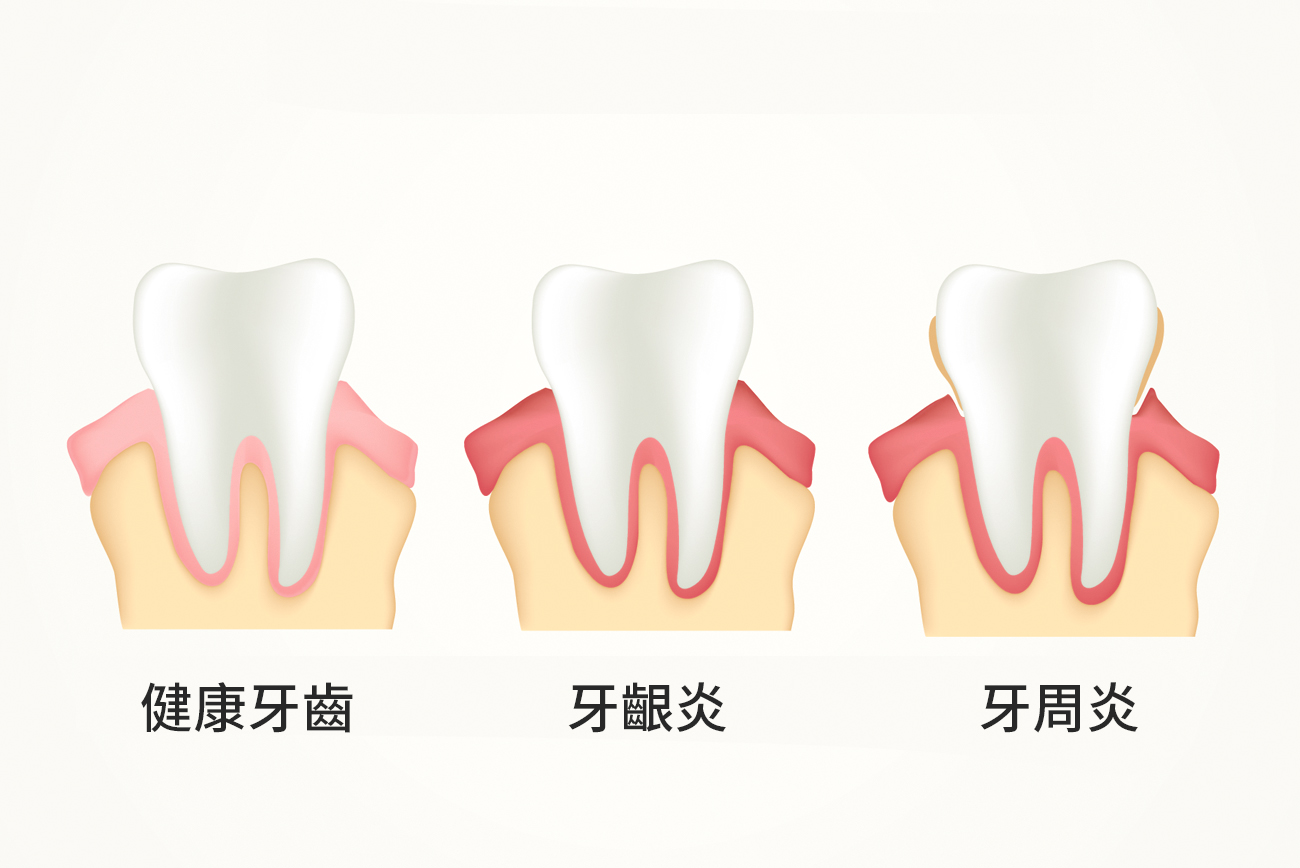

【黎医生教室1】华人好发的口腔疾病──牙周病

你刷牙时会流血吗?牙龈红肿吗?抱怨洗牙后吃东西开始塞牙缝还不如不洗吗?想当然认为人老了掉牙是正常现象吗?……如果以上任何一条说中了你,那么你可能罹患了好发于华人的口腔疾病──牙周病(Periodontal Disease)。

牙周炎是牙周组织(泥土)发生炎症、遭到破坏的疾病。长期不受控制的牙龈炎慢慢扩散到牙周膜,牙槽骨。牙周组织慢慢萎缩,如同泥土的流失。

牙周病有什么症状?

黎医生表示,牙周病最初并无任何症状,继而会出现牙龈发红、肿胀、疼痛,刷牙时开始流血。此时,牙槽骨完好,只是牙龈发炎,通过洁牙洗牙可以治愈。

如果不治疗,任由发展,经过10-20年,炎症进一步发展至深部,将导致牙槽骨萎缩,骨面下降,从1毫米,到2毫米,到3毫米……牙槽骨萎缩后,出现的空间由牙龈肿胀而填充,外表看起来牙齿紧密,没有缝隙,但实际上骨头与牙龈的比例已经改变了。牙槽骨继续萎缩下去,牙龈无法再填充时,牙齿间便出现了缝隙,牙周袋也渐渐形成了。

不同于牙龈发炎,牙槽骨萎缩后,病变无法回复,不能根治,治疗手段的作用只是阻止病变进一步发展,但已经消失的骨头不会再长回来了。

牙周病如何治疗?

黎医生表示,牙周病的主要治疗方法是洗牙。一般人每6个月洗一次,已经罹患牙周病的人需要每3-4个月洗一次。